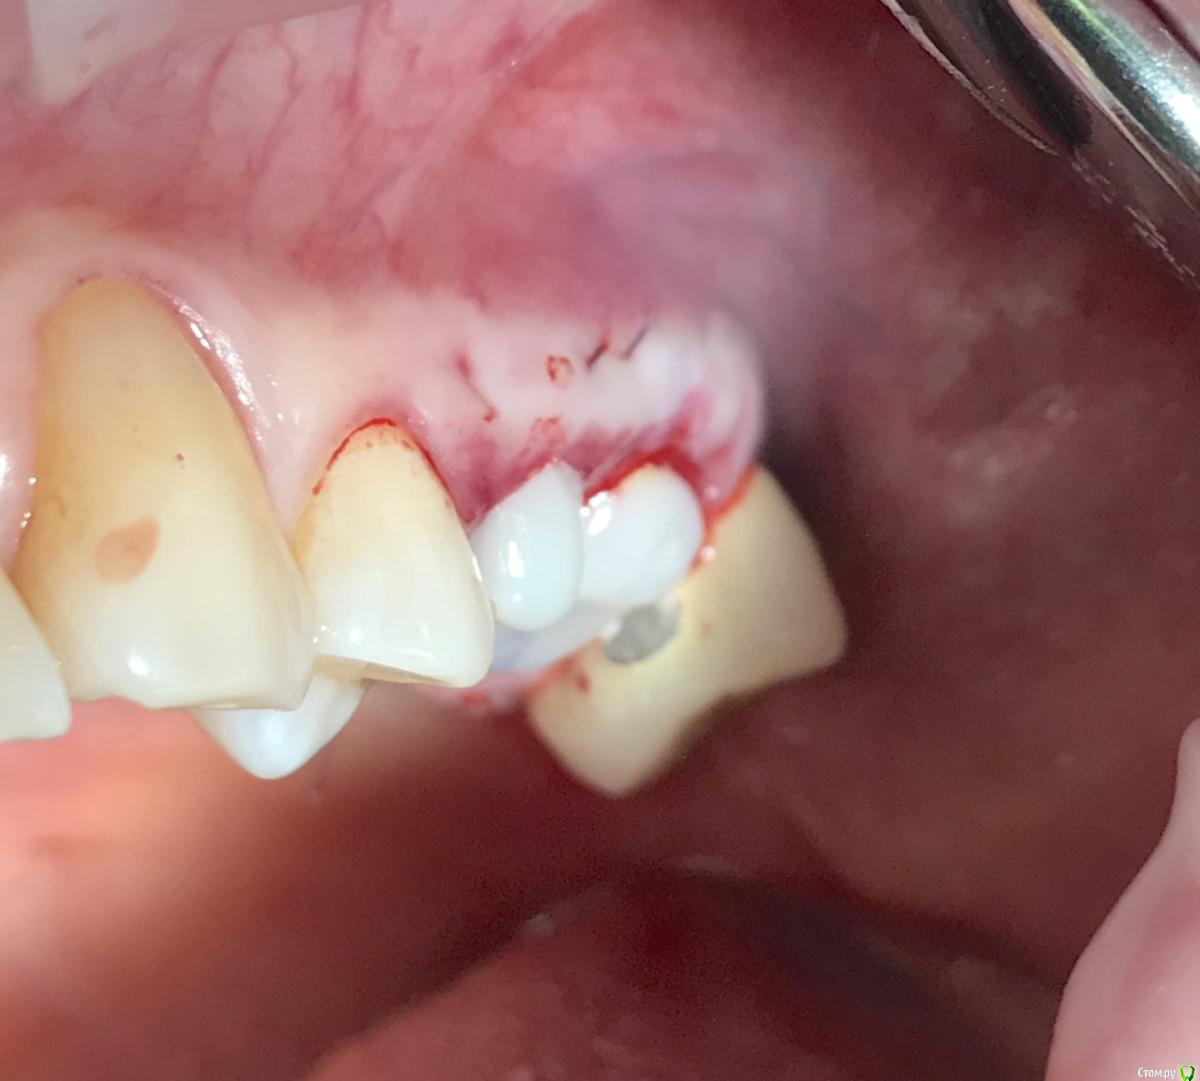

колесников Опубликовано 29 апреля, 2019 Поделиться Опубликовано 29 апреля, 2019 Модифицированый Ноймайер. Без радикса. Или это уже самостоятельный метод? Ссылка на комментарий

колесников Опубликовано 1 мая, 2019 Поделиться Опубликовано 1 мая, 2019 (изменено) Да вы правы,нужна связка. Вначале я использовал Колапол,но его хватало на неделю,потом все начинало дурно пахнуть. Однажды заметил что Альвастаз губка в герметично закрытой ране ,неведомым образом слипается с сдесневымиистенками лунки,да так плотно что трудно отделить и при этом сохраняет плотноэоастическую структуру. Как подтянуть мягкие ткани . Назовём это быстрый Ноймайер. В лунке имплант с широким но коротким фдм (или не коротким,край фдм должен быть в ровень или на 1мм ниже десневого края) . На спрессованный фрагмент Альвастаза наносим жидкотекучий композит,размером по форме лунки,но 1-2мм меньше,толщиной 2мм. Укладываем на фдм. Далее п-образными швами крест на крест придавливаем пробку вниз и соответственно десневой край подтягивается вверх. Если зашивать через край,фрагмент придавливается,но десна не подтягивается.Чем толще пробка,тем больше подтянуть можно,но и напряжение от швов больше,есть угроза прорывание. С шайбой из корня, если так делать, получается очень глубокая шахт с тонкими десневыми стенками,мне как то не понравилось. Фиксировать можно и к соседним зубам,но это не всегда возможно и это если на длительный срок. На швах достаточно 3-4ех недель если для консервации,2-3 если на фдм.После ушивания ещё заливаем сверху композитном,чтобы зафиксировать швы и перекрыть щели по периметру. Изменено 1 мая, 2019 пользователем колесников 1 Ссылка на комментарий